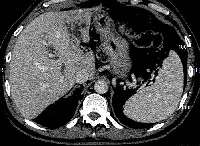

Πρόκειται για άνδρα ασθενή 62 ετών, ο οποίος υποβλήθηκε σε αξονική τομογραφία (εικόνα 1) για άτυπα γαστρεντερικά συμπτώματα και υπερχολερυθριναιμία. Διαπιστώθηκε μάζα μεγέθους 2,5 cm στον αριστερό (τμήμα 4) λοβό του ήπατος, η οποία εξορμούνταν από το χοληφόρο δένδρο, καταλάμβανε τη συμβολή του δύο ηπατικών πόρων, καθώς και το κεντρικό στέλεχος του αριστερού ηπατικού πόρου (χολαγγειοκαρκίνωμα τύπου Klatskin IIIB). Διενεργήθηκε ERCP (εικόνα 2) για τοποθέτηση παροχετευτικού stent και διόρθωση της υπερχολερυθριναιμίας. Υποβλήθηκε σε τυπική αριστερή ηπατεκτομή (τμήματα 1, 2, 3 και 4), εκτομή του εξωηπατικού χοληφόρου δένδρου έως τη Β' διαίρεση του δεξιού ηπατικού πόρου (εικόνα 3), καθώς και σε πλήρη λεμφαδενικό καθαρισμό του ηπατοδωδεκαδακτυλικού συνδέσμου (st 12A και st 12B). Η εντερική αποκατάσταση διενεργήθηκε με ηπατικονηστιδοστομία και με έλικα Roux μήκους 60 cm (εικόνα 4). Μετά την 4η μετεγχειρητική εβδομάδα, δόθηκε χημειοθεραπεία βασιμένη στο gemcitabine. Ο ασθενής παραμένει ελεύθερος νόσου.